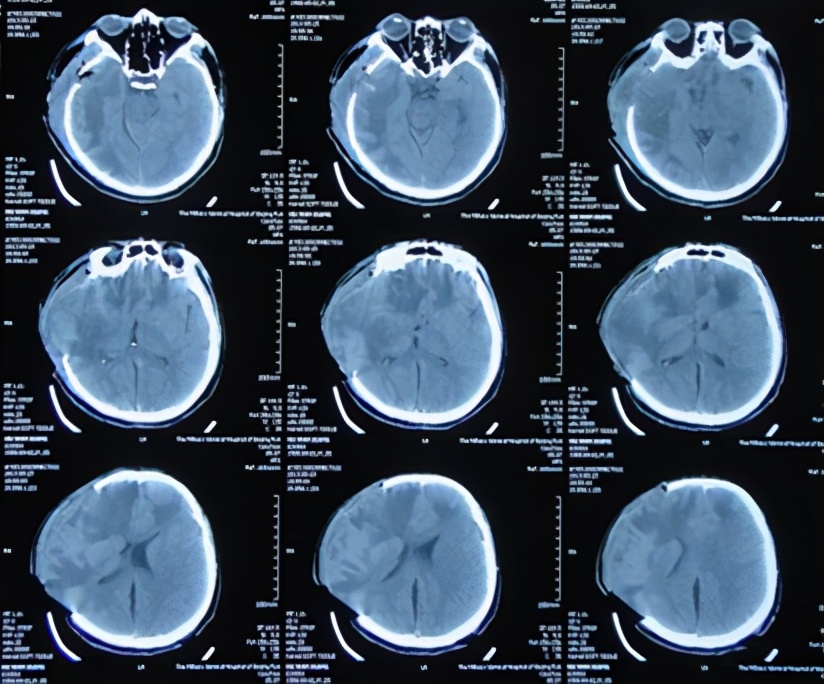

2013年11月21日即抗感染23天后即入院术后第51天(开颅术后第67天),给予试夹闭引流管观察骨窗情况。但在夹毕引流管次日患者出现右侧骨窗膨隆伴嗜睡,复查头CT:脑室系统扩张明显(图-16),再次给予开放脑脊液引流管。

图-16:2013年11月22日头CT

2013年12月17日即继续脑脊液引流25天后即入院术后第77天(开颅术后第93天),进行了侧脑室腹腔分流术,分流术后第1天2013年12月18日术后情况稳定(图-17)。

图-17:2013年12月18日

术后患者恢复良好,但仍间断头痛发作,在2013年12月25日即分流术后第8天(开颅术后第101天),复查头CT:脑室无异常(图-18)。

图-18:2013年12月25日头CT